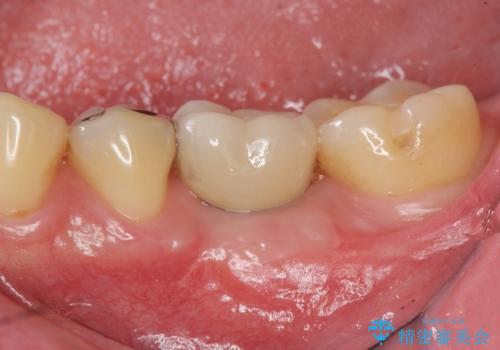

![[ 2次カリエス ]クラウンのグラつき クラウン下の虫歯再発の症例 治療後](https://seimitsushinbi.jp/wp/wp-content/uploads/2022/06/6554e5a0ec335a2529564005c968f18a-500x350.jpg?v=1655105463)